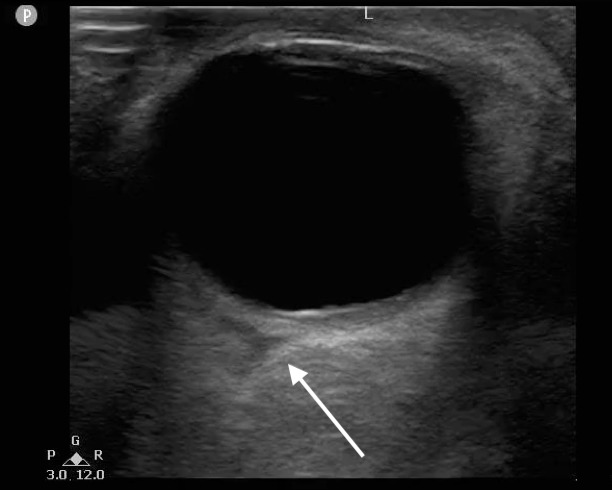

- It will appear as a hypoechoic area posterior to the globe and may distort the posterior globe.

- Figure 12. Triangular hypoechoic area (white arrow) suggestive of retrobulbar hematoma also known as “Guitar Pick Sign.”